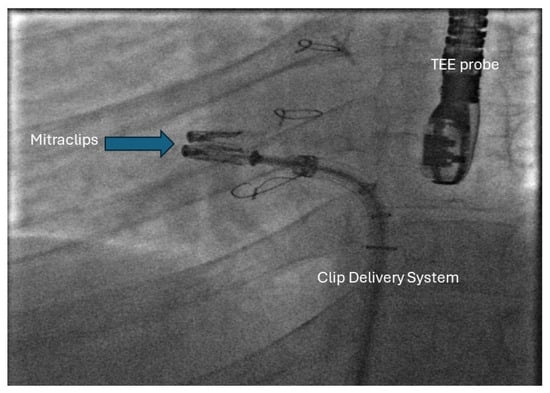

29. Percutaneous Intervention for AV Valve Regurgitation

- Kumar, P.; Gordon, B.M.; Kheiwa, A.; Abudayyeh, I. A case report of percutaneous MitraClip implantation in an adult with a double-outlet right ventricle. Eur. Heart J. Case Rep. 2023, 7, ytad247. [Google Scholar] [CrossRef] [PubMed]